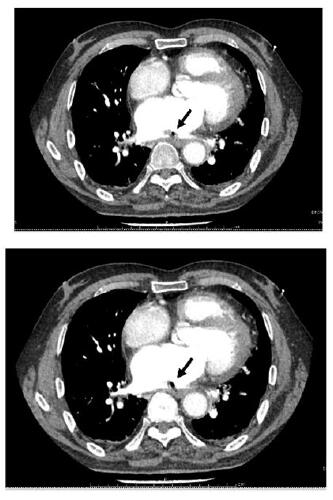

1 资料与方法患者,男,68岁;因“间断胸闷心慌1个月余,呕血伴发热1 d,意识障碍12 h”收入华中科技大学同济医学院附属同济医院。患者一个月前自觉胸闷、心慌,至当地市级医院诊断为“房颤、冠状动脉粥样硬化”,入院前34 d行房颤消融术+冠脉造影术,术后口服达比加群酯110 mg 2次/d,术后3 d再次因胸闷心慌至当地县人民医院住院治疗,给予对症治疗,症状可缓解。入院2 d前再次出现胸闷心慌等不适,入院前1日下午4时呕血约300 mL,伴寒战高热,最高可达39.5 ℃,并于入院当日中午12时出现意识障碍,言语不清,为求进一步治疗转至本院急诊科。急查头部CT示:脑萎缩,脑白质病;右侧半卵圆中心及左侧基底节区片状低密度影,考虑为缺血梗死灶;右侧小脑半球片状低密度影,考虑脑梗死、软化灶形成。后患者意识障碍较前缓解,急诊科收治入院。既往史:高血压史十余年,5年前脑梗死病史,10年前行腰椎间盘突出手术治疗,吸烟30余年,每日一包,饮酒30余年,每日250 mL,戒酒10年。入院体格检查:患者意识清醒状态,言语沟通不畅,心电监护提示:血压105/80 mmHg,脉搏87次/min,SPO2 100%,心率18次/min;双侧瞳孔等大等圆,直径2.5 mm,对光反射存在,双肺呼吸音粗, 未闻及啰音;心音可,律齐,未闻及杂音;腹软,移动性浊音阴性,肠鸣音正常。四肢无畸形,四肢活动无障碍,双下肢无水肿,生理反射存在,双侧巴氏征阳性可疑。患者入院后完善相关检查。血常规:白细胞计数23.23×109/L,血红蛋白93.0 g/L,血小板计数117.0×109/L,谷丙转氨酶14 U/L,谷草转氨酶17 U/L,尿素15.93 mmol/L,肌酐103 μmol/L,葡萄糖10.84 mmol/L,N-末端脑利钠肽前体(N-terminal pro brain natriuretic peptide,NT-proBNP)5 577 pg/mL,降钙素原32.51 ng/mL,高敏心肌肌钙蛋白I 413.9 pg/mL,血乳酸2.22 mmol/L。心脏超声检查示左房扩大55 mm,心脏收缩力下降,左心EF值40%。患者入院后给予抗感染、抑酸、营养支持等治疗,患者于入院当晚9时出现剧烈咳嗽,后意识障碍再次加深,遂行颅脑CT检查,示左侧大脑内气体栓塞(图 1);神经内科会诊,考虑脑内气体栓塞。给予患者头低脚高位,降低颅内压等治疗,次日晨复查胸部增强CT,示左房改变,考虑左房破食管瘘并左房血栓形成(图 2),诊断为“心房食管瘘”,请胸外科会诊意见:患者颅脑内积气吸收后,可进行心脏食管手术。患者于入院第2天上午8时出现呼吸衰竭,行气管插管术,呼吸机辅助呼吸,患者家属于当日下午因个人原因办理出院。

| 不同层面内左心房内低密度影,考虑心房食管瘘后气体残留,周围有血栓形成(黑色箭头示) 图 2 患者胸部增强CT结果 |